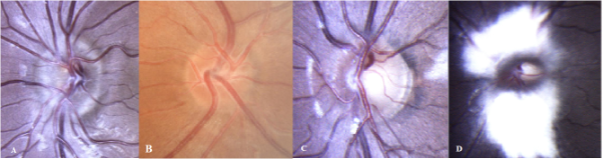

Ophthalmoscopically, Frisen grading is used to grade papilledema [Fig 1] and is shown below in Table 2[1], which was explained by Frisen way back in 1982.

Very early papilledema Nasal obscuration of disc margins, with halo, without elevation of the disc or opacification of the Nerve fiber layer |

Early papilledema Complete peripaillary halo, elevated disc, obscuration of all borders |

Moderate papilledema Above + obscuration of one or two segments of blood vessels over the disc |

Marked papilledema Above + total obscuration of a major blood vessel over the disc |

Severe papilledema All vessels are obscured by edema Anteriorly elevated, dome-shaped disc Cup is filled and obliterated |

Table 2: Frisen grading of papilledema.[1]